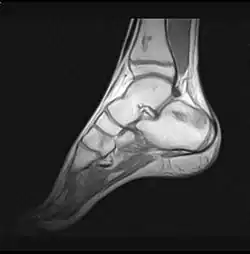

- Stadium ARCO 0

Im Anfangsstadium sind in konventionellen Röntgenaufnahme keine krankhaften Veränderungen zu erkennen. In seltenen Fällen ist eine dezente Auflockerung der Knochenfeinstruktur (Trabekel) in dem betroffenen Areal zu erkennen: das Ausmaß dieser Auflockerung ist jedoch zumeist so gering, dass es nicht sicher erkannt werden kann. In der Kernspintomographie (MRT) ist in diesem Stadium ein Bild analog dem Knochenmarködem (KMÖ, transiente Osteoporose; bone marrow edema, BME) zu erkennen. Unter Verwendung der short tau inversion recovery (STIR) Aufnahmesequenz wird eine Signalhyperintensität (helles Aufleuchten im Graustufen-Kernspinbild) festgestellt (vergleiche Bild 1a und 2 helle Ränder). Eine sichere Unterscheidung zwischen dem prinzipiell reversiblen Bild eines KMÖ/BME und dem Stadium ARCO I einer aseptischen Knochennekrose ist nicht mittels des Kernspintomogramms möglich.